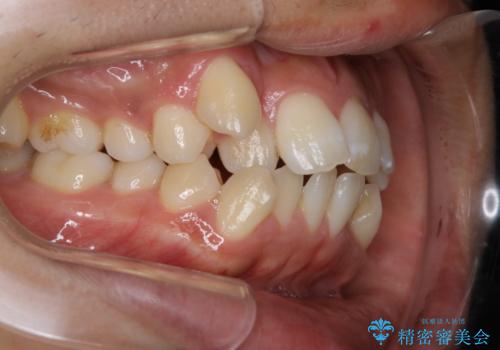

- オーディションで歯並びを指摘されたことから一念発起して矯正治療を行う事にした方です。

親知らずと、前から4番目の歯を抜歯してワイヤー装置による矯正治療を行いました。

人前に出ることが多いため、当初は目立たない装置をご希望されていましたが、歯の移動距離が大きいため効率よく歯を動かせる表側の装置での治療をお勧めしました。すれ違ってしまっていた奥歯もしっかり治すことができました。